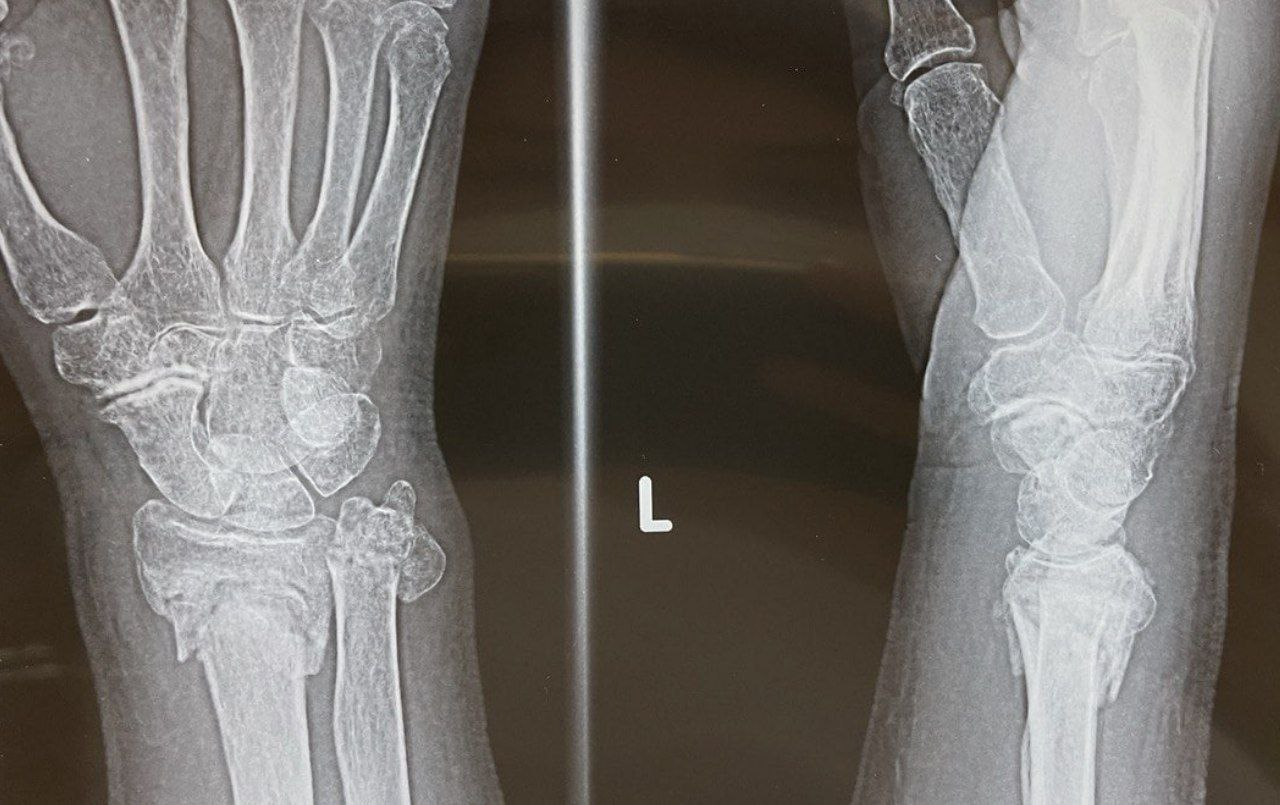

Dr. TEOРечь идет о женщине 74 лет с непримечательной неврологической и ортопедической историей, которая в марте 2021 года падает на вытянутую руку и в результате получает перелом лучевой кости в типичном месте и дистального отдела локтевой кости. В травмпункте конечность была фиксирована в гипсовую лонгету на 4 недели.

На первом приеме в апреле 2021 пациентка оценивала боль на 7 из 10 (по шкале ВАШ), функциональность кисти по опроснику QuickDASH (max 100) = 93 балла. Конечность была горячей, отечной, ригидной, с гиперчувствительностью на тактильные раздражители. Подвижность пальцев резко ограничена ввиду боли и отечности.